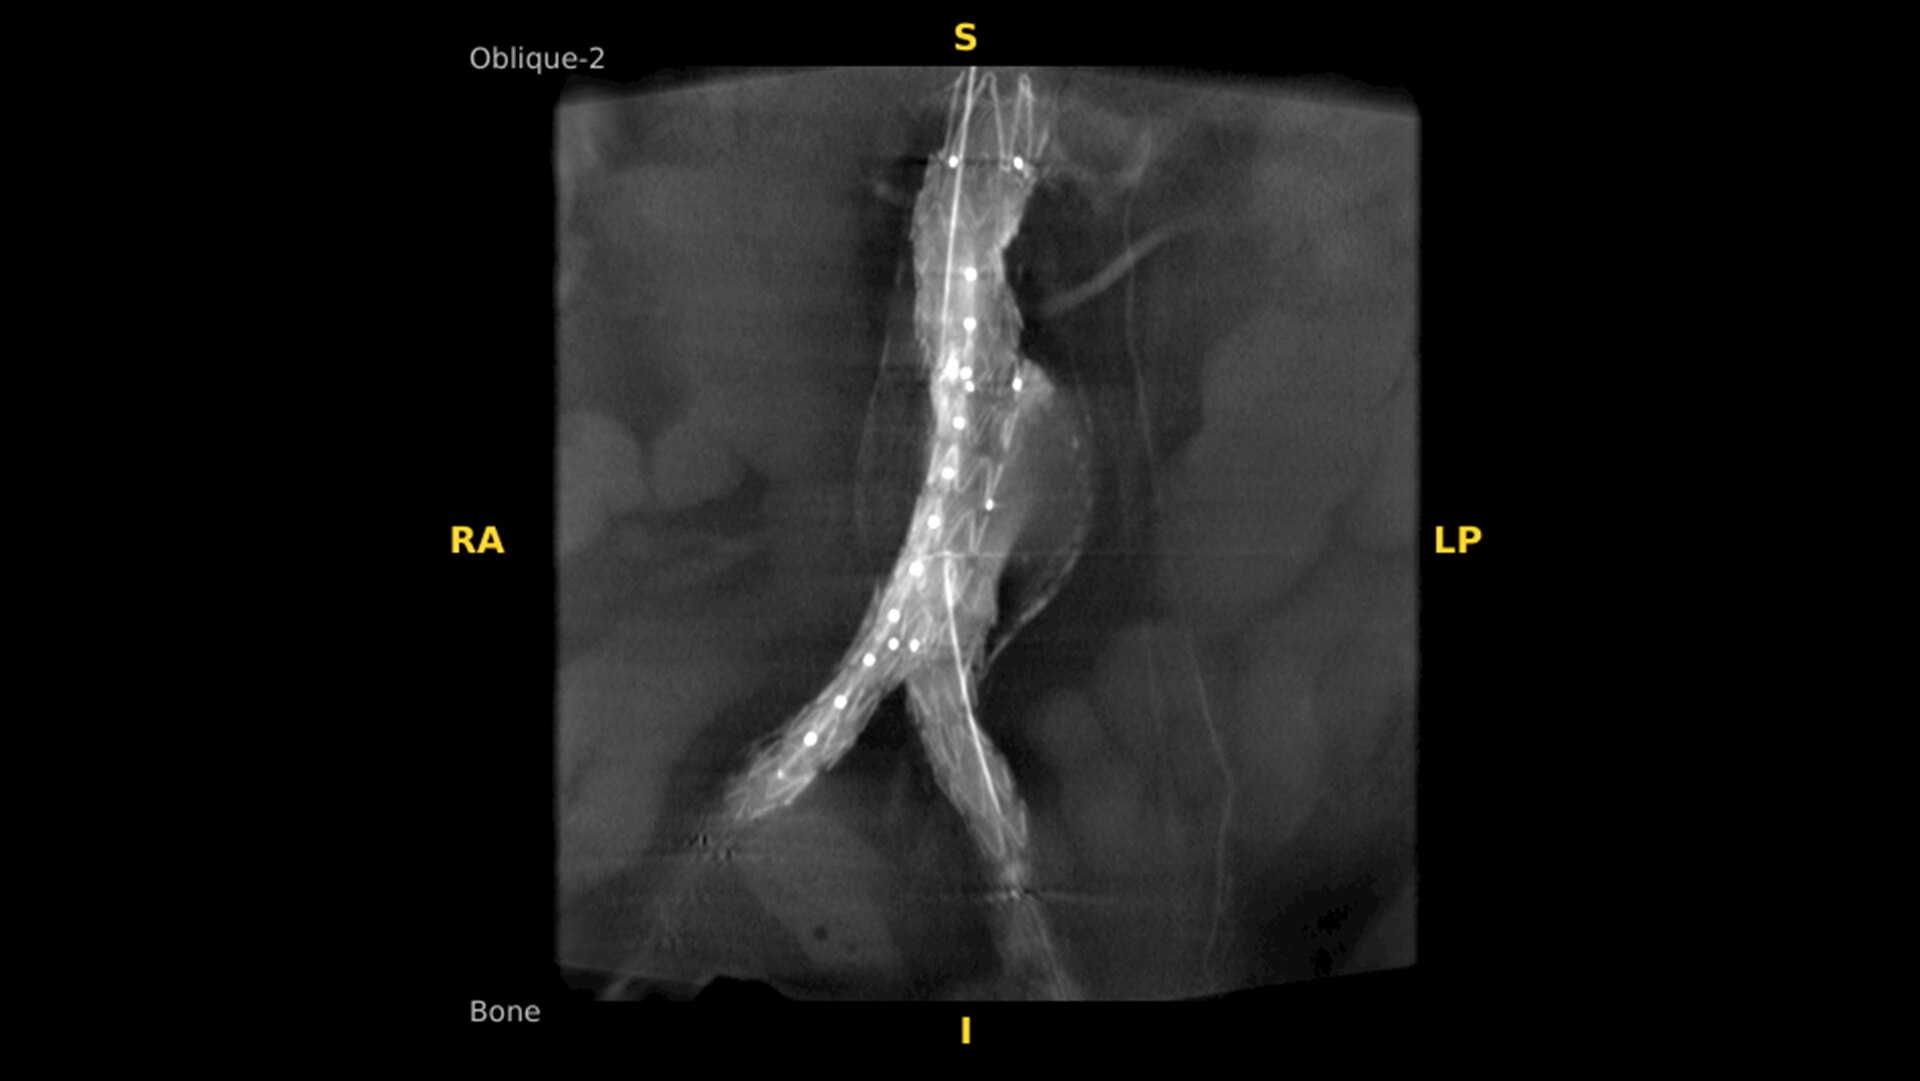

A 3D C-arm for every day:  from spinal fusion or orthopedic fractures to angiogram and stent placement

True 3D and 2D imaging flexibility. Transitioning quickly and easily provides greater efficiency and versatility for a wide range of clinical applications from spine and orthopedics to cardiac and vascular. Finally, a 3D C-arm that every surgical suite deserves.